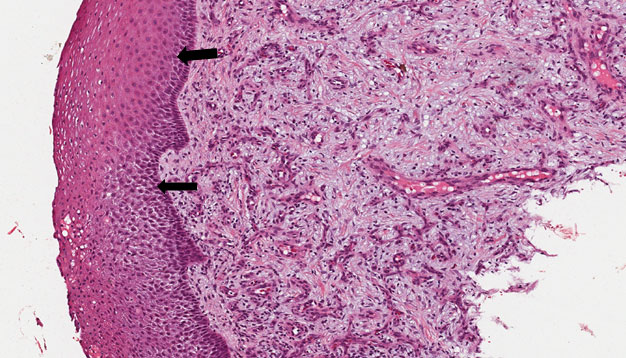

9.4 Lesão periférica de células gigantes

Descrição

Fragmento de mucosa bucal revestida por epitélio estratificado pavimentoso em áreas hiperceratinizado e hiperplasiado (Figura 10). Na lâmina própria adjacente ao epitélio observamos uma faixa de tecido conjuntivo denso normal. Mais na profundidade nota-se a proliferação de fibroblastos volumosos, inúmeras células gigantes multinucleadas, fibroblastos volumosos e vasos(Figura 10 — setas). Hemorragia e deposição de hemossiderina na periferia da lesão completam o quadro.

Dados importantes para o diagnóstico

Fibroblastos jovens (Figura 11 — setas) proliferando no tecido conjuntivo, células gigantes multinucleadas (Figura 11 — asterisco) no tecido conjuntivo, vasos circundantes, extravasamento de hemácias, pigmentação por hemossiderina.

Figura 10

Figura 11